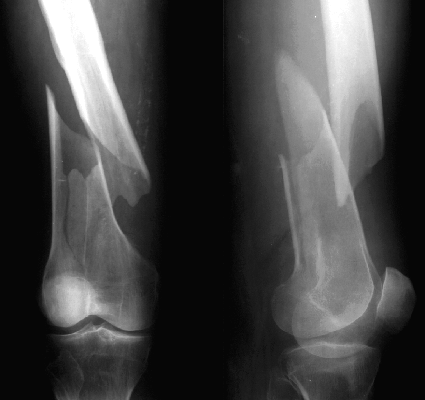

Low Femoral Fracture